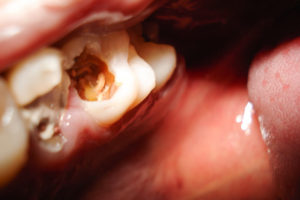

L’odontoiatra attraverso l’utilizzo di strumenti meccanici e manuali elimina il tessuto cariato (molle) ottenendo una superficie dura e detersa sulla quale apporrà, a piccoli strati, la resina composita fino a riprodurre l’esatta anatomia del dente, mimetizzando completamente l’otturazione.

Il vantaggio di tale metodica consiste nella rapidità d’esecuzione ed e’ indicata principalmente nei processi cariosi di ridotta estensione.